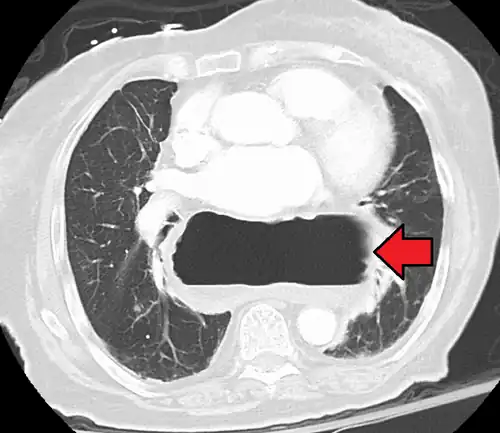

A hiatal hernia as seen on CT -

A large hiatal hernia as seen on CT imaging -